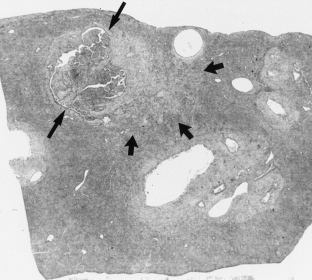

Fig. 1.